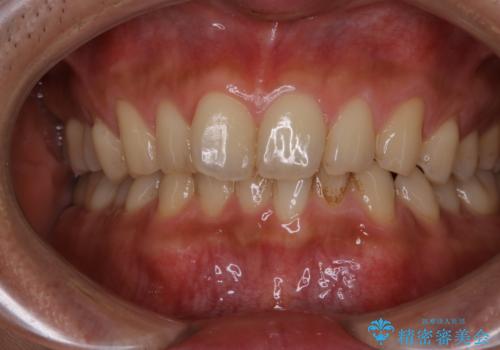

毎日コーヒーを飲む 歯を白くしたい

- 毎日コーヒーを飲むため、歯の着色がとっても気になるとのことでした。歯科でのクリーニングは2.3年ぶりのため全体的にきれいにしてほしいとのことでした。

PMTC60分コースを行いました。

またPMTCを行うことで、ご自身本来の歯の色になり自然な明るさになります。